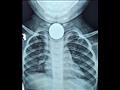

وأضاف أن الطفلة كانت تستجيب للعلاج بشكل جزئي ثم بدأت تعانى من صعوبة في التنفس ونوبات اختناق وكانت تأخذ جلسات استنشاق وبعد معاناة لمدة 70 يومًا من تعب الطفلة طلب الطبيب المعالج عمل أشعة على الصدر وأظهرت وجود جسم معدني يشبه العملة المعدنية في المريء .

وأضاف "الرفاعي" أنه جرى استقبال الطفلة في مستشفى الأطفال وإجراء أشعة مقطعيه لها أظهرت وجود العملة المعدنية في المريء.